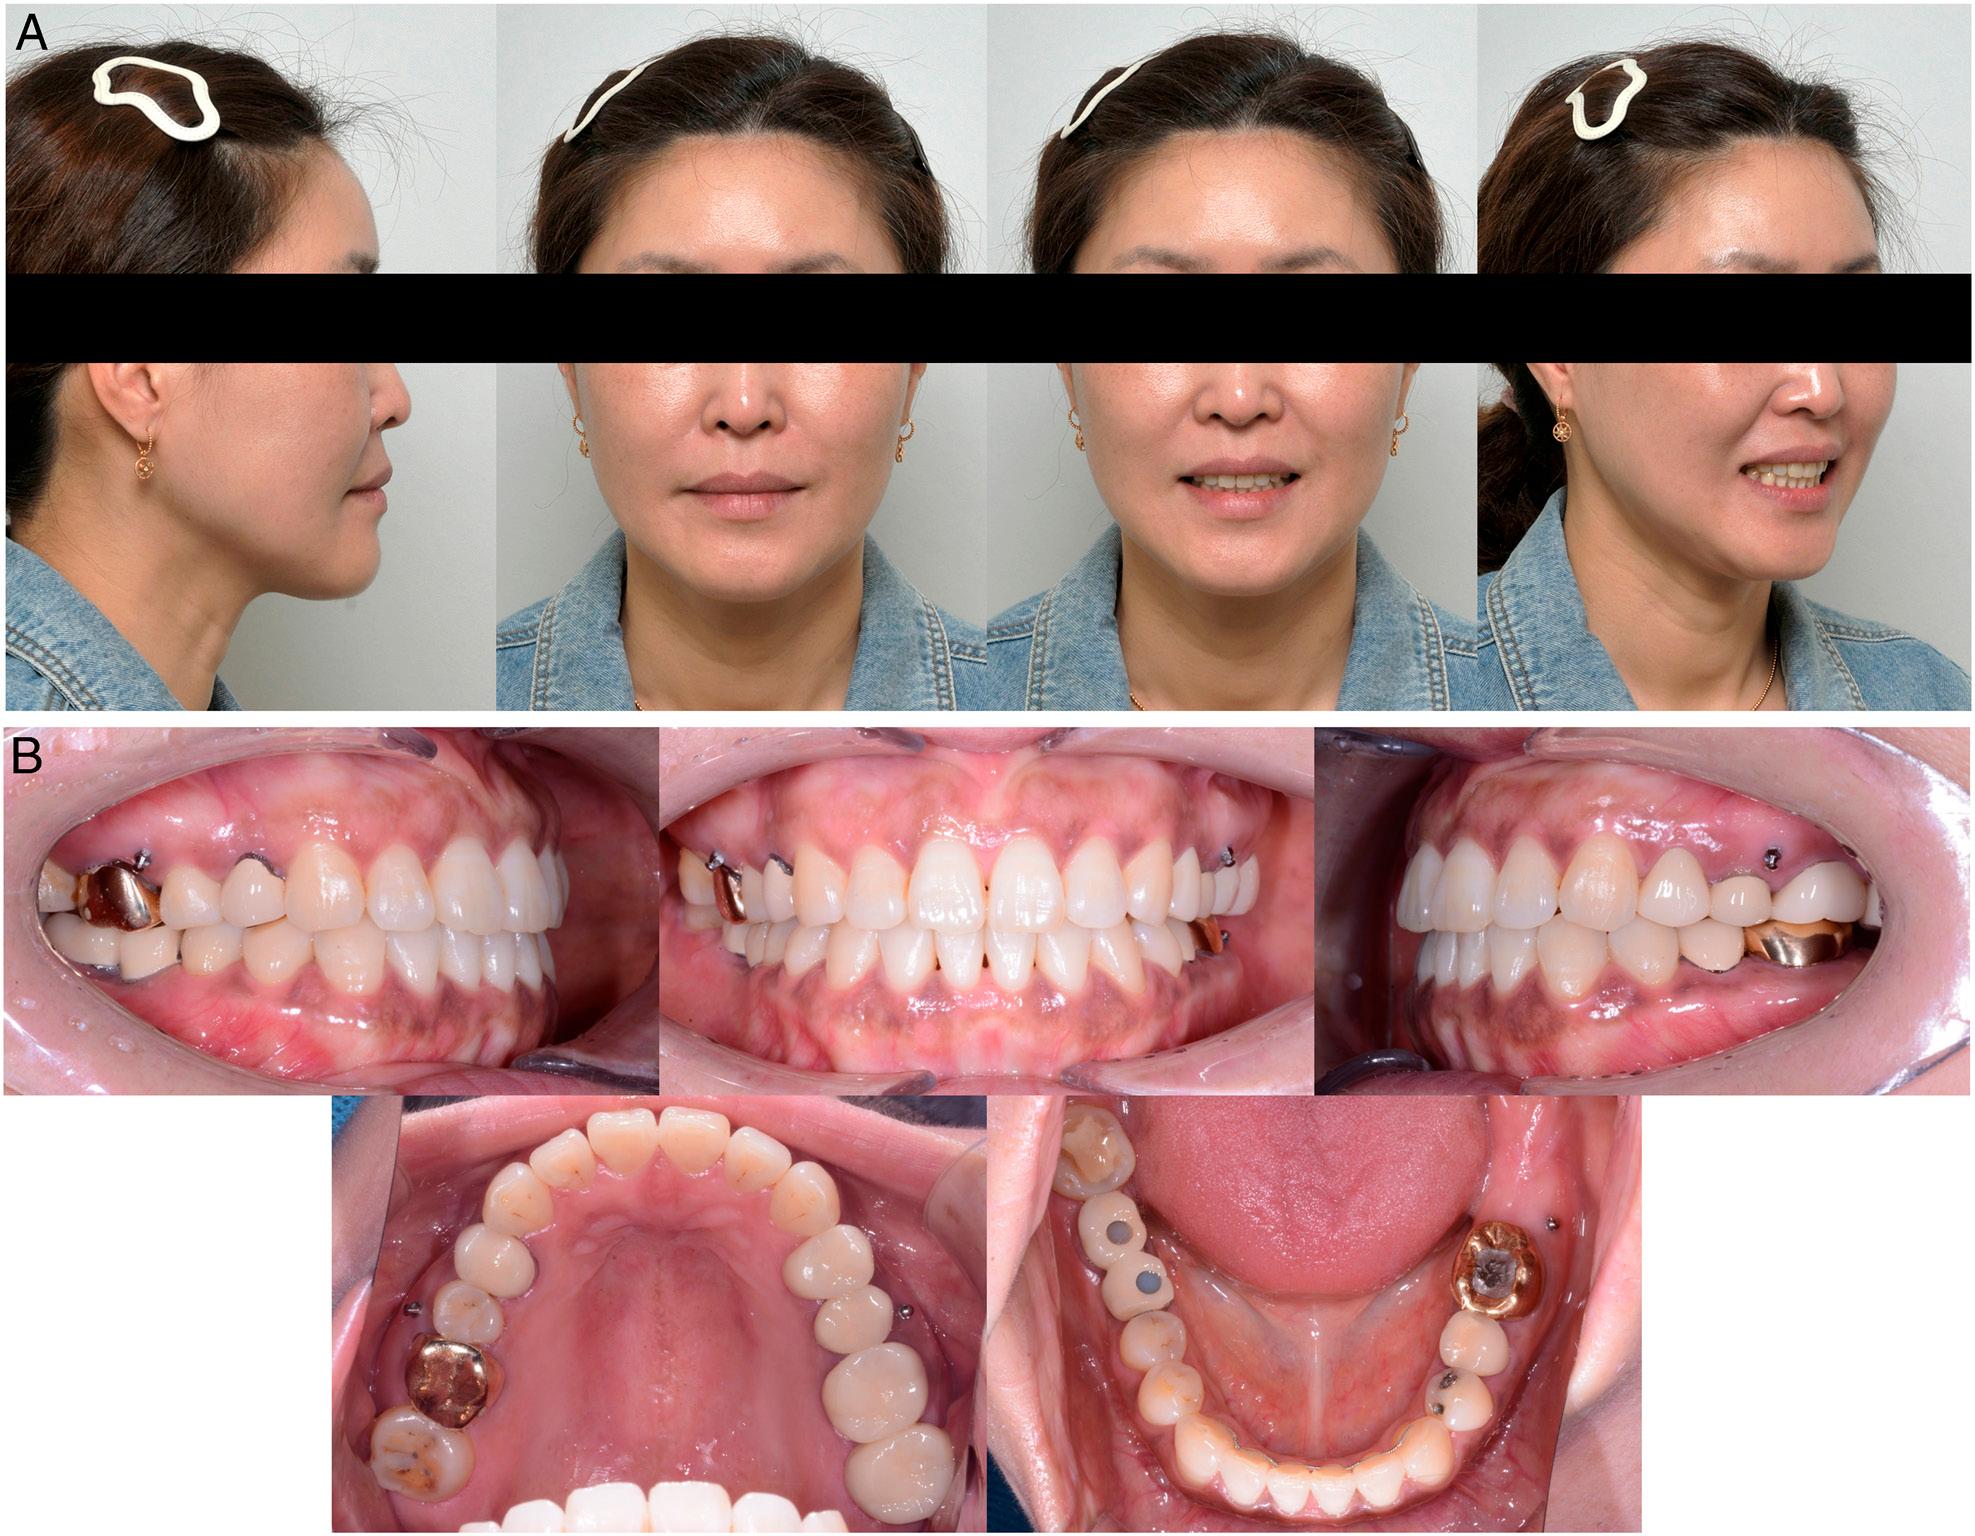

Figure 1.